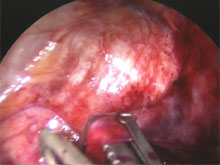

Durch zwei 5 mm große Hautschnitte in der Axelhöhle werden ein Endoskop mit Fernsehkamera und ein Clipapplikator in den Brustkorb eingeführt. Die Lunge wird durch Insufflation von Kohlendioxid vorübergehend weggedrängt. Die den Arm versorgenden Ganglien werden durch Anbringen eines Metallclips komprimiert. Dadurch wird die Nervenleitung unterbrochen. Bei Operation wegen Hyperhidrosis wird lediglich das vierte Thorakalganglion geclipt, um Nebenwirkungen wie kompensatorisches Schwitzen an anderen Körperregionen möglichst gering zu halten. Der Eingriff dauert nur wenige Minuten und wird simultan an beiden Armen durchgeführt.